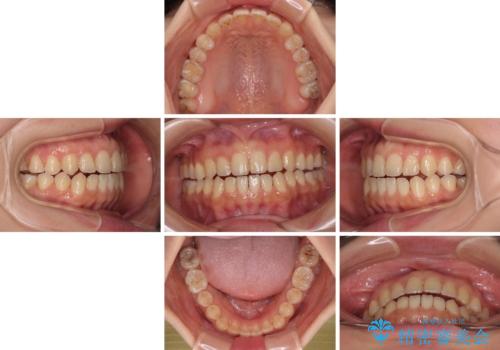

前歯のオープンバイト インビザラインで咬み合わせを改善

- 20代女性

- インビザライン

- 1年6ヶ月

- 5-10回

- 前歯の開咬を気にして来院された患者様です。

開咬の治療は、前歯を閉じるように動かすとともに、上下臼歯を圧下(骨内にめり込ませる)させることで進めて行きます。

インビザラインは臼歯の圧下を効果的に行えるため、インビザラインを用いて矯正治療を行うこととしました。